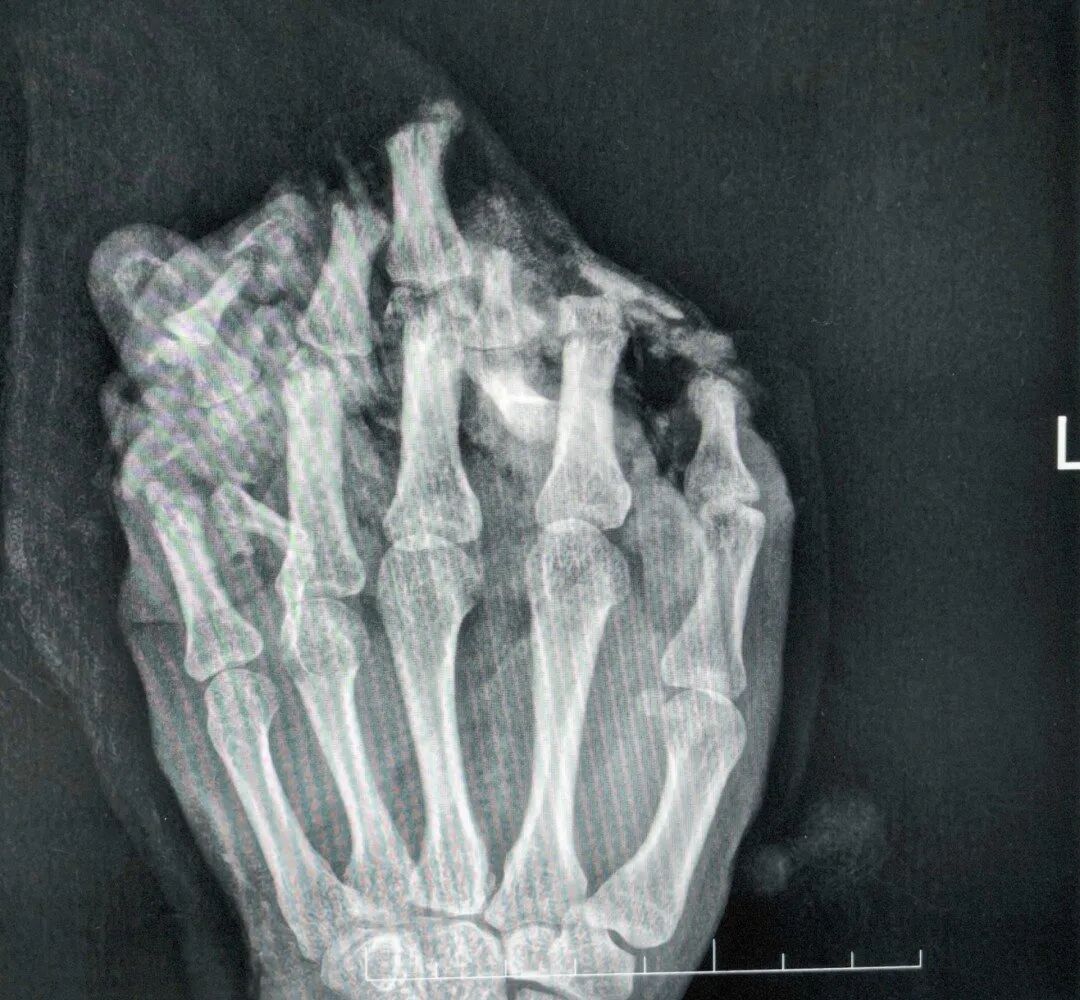

几个月前,24岁的工人小王工作时,左手不慎被机器碾压,导致左手严重受伤,手掌、手背、各指掌侧及背侧皮肤脱套流血、疼痛,被紧急送到东莞市横沥医院。

医生诊断他为:1.左手掌、手背,示指中指环指小指掌侧及背侧皮肤毁损脱套伤;2.左手掌、手背及各指肌腱神经血管损伤;3.左手多发性开放性指骨骨折伴毁损;4.左拇指末节指腹皮肤、软组织缺损;5.左拇指固有神经断裂;6.左拇指甲床裂伤。

医院随即为小王做了手术,术中,医生们完成了彻底的清创,修复了骨折、断裂的肌腱与神经。